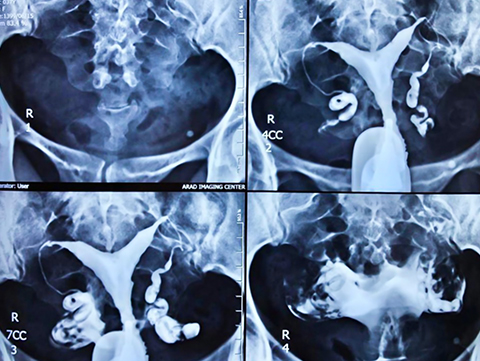

هیستروسالپنگوگرافی توسط رادیولوژیست انجام می شود. معاینه بدون بیهوشی انجام می شود. بیمار در موقعیت "زنان و زایمان" مستقر می شود. پزشک اسپکولوم را قرار می دهد، دهانه رحم را ضد عفونی می کند و سپس یک پروب را با روش طبیعی وارد رحم می کند. او به تدریج ماده حاجب را تزریق می کند. به طور معمول، ماده حاجب به تدریج رحم و لوله های فالوپ را کدر می کند تا زمانی که به حفره صفاقی منتقل شود.

چندین عکس رنگی رحم قبل، حین و بعد از تزریق محصول گرفته می شود و این در موقعیت های مختلف:

اشعه ایکس بدون آماده سازی (جستجو برای کلسیفیکاسیون لگن)؛

اشعه ایکس پر شدن ضعیف (پولیپ ها یا فیبروم های زیر مخاطی را برجسته می کند).

اشعه ایکس پر شدن لوله (ارزیابی وضعیت مخاط لوله).

عکس پروفایل (ارزیابی موقعیت رحم و مسیر لوله های فالوپ)؛

اشعه ایکس دیررس (بررسی گردش خون صفاقی، جستجو برای چسبندگی لگن).

انسداد لوله: یک یا هر دو لوله "مسدود" هستند. انسداد ممکن است پروگزیمال (روزنه لوله داخلی) یا دیستال (روزنه لوله خارجی) باشد. انسداد دیستال می تواند متوسط باشد، اجازه عبور کمی را می دهد (به نام فیموز) یا کامل، بدون عبور (به نام هیدروسالپینکس).

پولیپ داخل رحمی؛

فیبروم زیر مخاطی (تومور خوش خیم رحم)؛

Synechia (چسبندگی و چسبندگی در حفره رحم یا در دهانه رحم)؛

ناهنجاری مادرزادی رحم (سپتوم رحم، رحم دو شاخ).